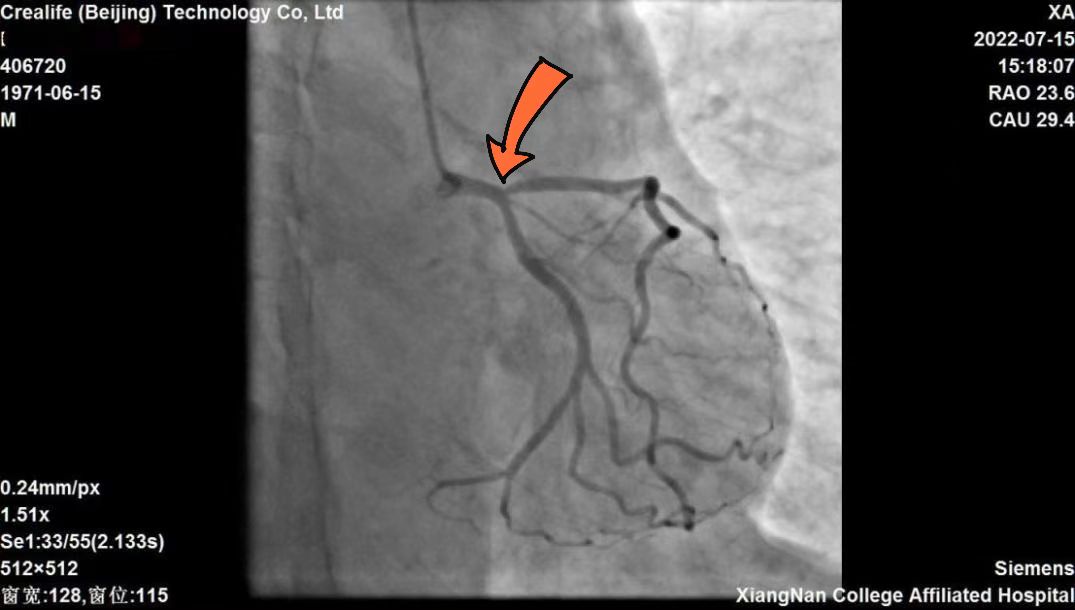

51岁的患者邓某,因反复活动时胸闷胸痛半月有余,遂入湘南学院附属医院心血管内科求诊治疗。接诊后,经心电图和冠脉造影检查显示:邓某左前降支开口70%狭窄,为临界病变,被诊断为冠心病、不稳定型心绞痛。按照传统治疗观念,邓某可能需要植入冠脉支架以改善心肌缺血。

▲患者冠脉造影显示箭头所指位置为病变处

那么,是否需要左冠脉支架手术?患者狭窄病变处又是否会引起心肌缺血?心血管内科团队经过反复对比和分析,发现邓某左前降支处狭窄程度虽严重,但未必是非植入支架不可的状态。为了进一步求证治疗方向,心血管内科团队决定采用最新的caFFR检查技术,为患者行冠脉测定血流储备分数测量,避免不必要的支架植入。

▲caFFR测定显示值0.87 (大于参考值0.80),无需行介入治疗

与家属充分沟通同意后,心血管内科团队为患者行冠脉造影下caFFR测定。整个测定过程非常顺利,经测量显示:前降远端的caFFR值为0.87,明显大于指南推荐参考值0.80,邓某血管狭窄程度看似严重,但病变冠脉血流储备功能良好,依据临床指南参考判断,无需植入支架手术治疗,拟予患者药物保守治疗。